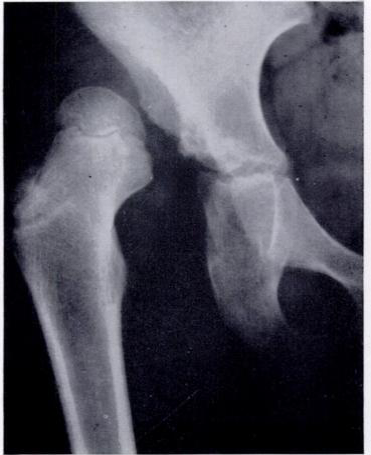

Dislocated right femoral head with very shallow acetabulum

Dislocated right femoral head with very shallow acetabulum. Red line outlines the stretched out capsule.